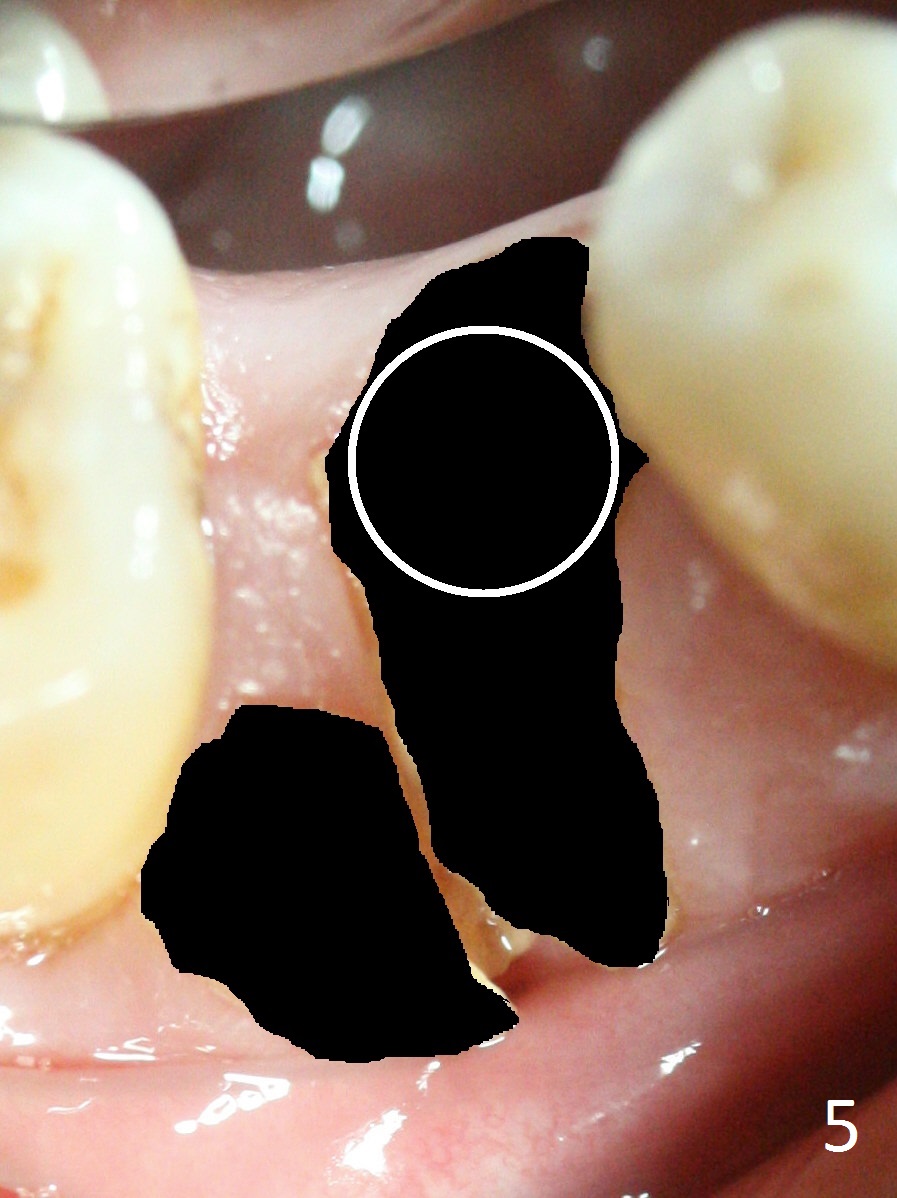

When a 46-year-old man presents with new patient examination, the tooth #29 has root fracture with a crown in place (Fig.1). A year later when he returns for #32 extraction, the crown is lost with displacement of the distobuccal (Fig.2,3 DB) portion of the root. The gingival recession is severe. When the root is removed, an implant will be placed as lingual as possible (Fig.5 white circle). Magic Drill 3.3 mm will be used for osteotomy (without 1.6 mm drill). Trajectory and depth will be tightly controlled while starting and advancing the drilling (one shot). Take PA following partially inserting a 4x11 mm dummy implant.